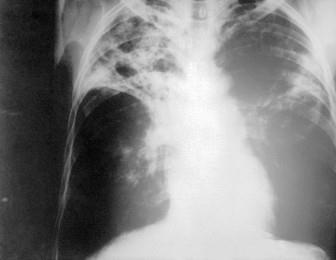

问题 患者,男性,21岁,咳嗽伴午后低热1周入院,X线胸片如图所示,最可能的诊断是 ( )

选项 A、肺结核 B、肺癌 C、肺炎 D、支气管扩张 E、脓胸

答案 A